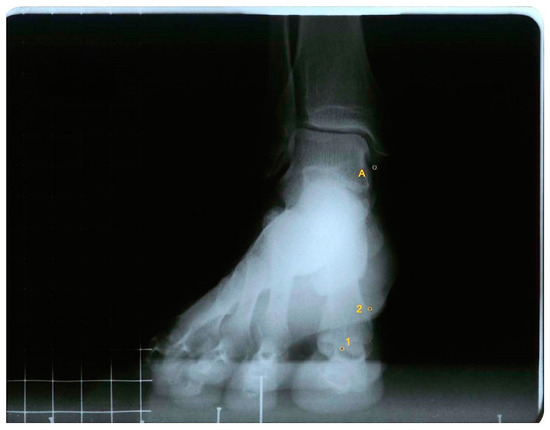

For measurements, the AutoCAD® software was used (AutoCAD 2016; Autodesk Inc., San Rafael, CA, USA). One point was drawn in the intersesamoid crest (point 1) and one in the superomedial tubercle where the medial collateral ligament of the first metatarsophalangeal joint begins (point 2). A third point was marked in the most inferior tip of the tibial malleolus (point A), which acted as a fixed point (Figure 1).

To obtain the first ray displacement in the sagittal plane the distance was measured in millimeters from point A to point 1, in the three positions, plantarflexed, neutral, and dorsalflexed. To measure the movement in the frontal plane, two lines were drawn to find the angle that formed between them: one line between points 1 and 2, and the other being a horizontal line, parallel to the ground (Figure 2 and Figure 3).

Figure 1. Antero-posterior radiograph of a participant with the first ray in a neutral position, showing point A (most distal point of the tibial malleolus), point 1 (intersesamoid crest), and point 2 (superomedial tubercle of the head of the first metatarsal).